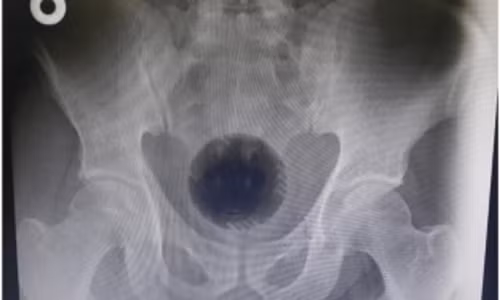

| Ảnh chụp X-quang của người đàn ông. |

Bác sĩ Mohammad Athamnah, người tiếp nhận trường hợp này, đã tiến hành chụp X-quang cho người đàn ông và nhận thấy kích thước của quả bóng trong người anh ta tương tự như quả bóng tennis. Quả bóng này bị kẹt trong cơ thể làm tắc hoàn toàn trực tràng, khiến người đàn ông không thể đi vệ sinh được.